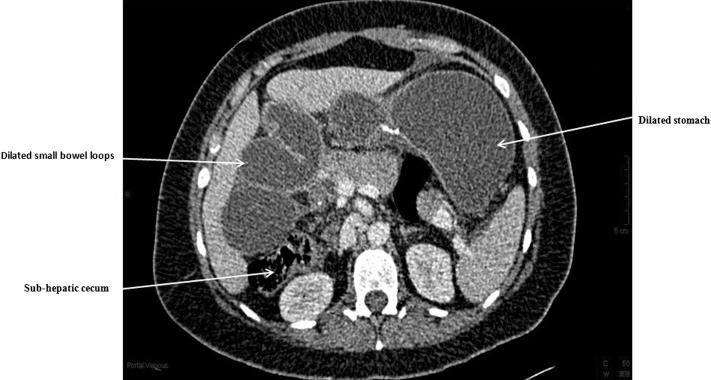

A 40-year-old woman presented with small bowel obstruction caused by an internal hernia through Peterson's defect. The patient was known to have midgut malrotation (MM) and also had laparoscopic Roux-en-Y gastric bypass for morbid obesity 6 years prior. An open revision of Roux-en-Y gastric bypass was performed as a result of ischemia of alimentary limb. She made a slow but uneventful recovery and was discharged home. MM is a rare congenital anomaly that requires the surgeon to be well aware of the unique variation in anatomy to perform a mirror image of the routine Roux-en-Y gastric bypass. At the end of this case report, we present a short literature review of published data related to MM encountered during Roux-en-Y gastric bypass.

一名40岁女性因经彼得森间隙的内疝导致小肠梗阻就诊。该患者已知患有中肠旋转不良(MM),且6年前因病态肥胖接受了腹腔镜Roux-en-Y胃旁路手术。因营养支缺血,对Roux-en-Y胃旁路进行了开放修复术。她恢复缓慢但过程顺利,随后出院回家。MM是一种罕见的先天性异常,需要外科医生充分了解解剖结构的独特变异,以便实施常规Roux-en-Y胃旁路手术的镜像操作。在本病例报告末尾,我们对Roux-en-Y胃旁路手术中遇到的与MM相关的已发表数据进行了简短的文献综述。